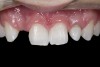

(13.) Deficient ridges in the areas of the missing lateral incisors.

Figure 13

(14.) Occlusal view. Some form of augmentation would be needed if implants were being considered.

Figure 14